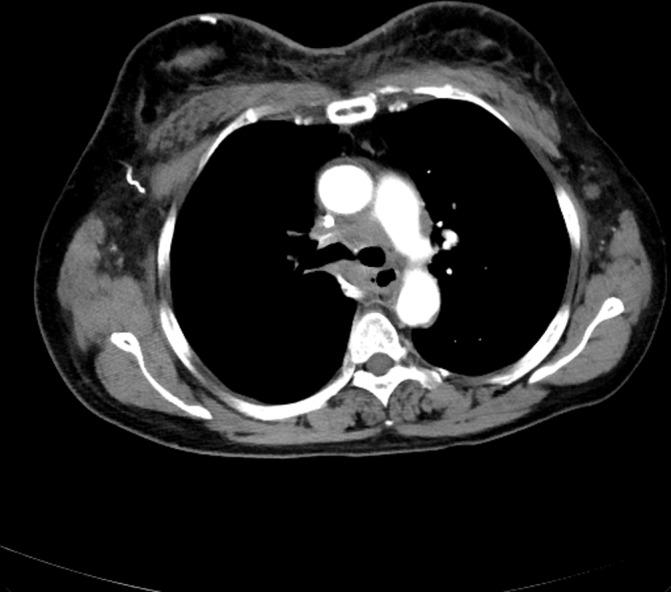

Cutaneous lymphangitis carcinomatosa (CLC) is a rare form of cutaneous metastasis that causes lymphoedema and various eruptions. We report a case of lung cancer with CLC that caused both superior vena cava (SVC) stenosis and cervicofacial oedema, suggestive of SVC syndrome. A 64-year-old woman with lung adenocarcinoma presented with cervicofacial oedema and erythema, followed by severe dyspnoea 2 months after four cycles of carboplatin, pemetrexed and bevacizumab triplet therapy. Although chest CT indicated SVC stenosis, cervicofacial oedema remained despite treating the SVC stenosis via balloon dilation. A skin biopsy of the erythematic sample confirmed CLC as the cause of the patient's symptoms. CLC should be considered as a differential diagnosis of cervicofacial oedema in addition to SVC syndrome, especially when it is observed in combination with skin erythema and induration. Moreover, a skin biopsy should be performed promptly for accurate diagnosis of CLC and to decide on appropriate treatment.

摘要

皮肤淋巴管癌病(CLC)是一种罕见的皮肤转移形式,可导致淋巴水肿和各种皮疹。我们报告一例患有CLC的肺癌病例,该病例导致上腔静脉(SVC)狭窄和颈面部水肿,提示SVC综合征。一名64岁的肺腺癌女性患者在接受四个周期的卡铂、培美曲塞和贝伐单抗三联疗法后2个月,出现颈面部水肿和红斑,随后出现严重呼吸困难。尽管胸部CT显示SVC狭窄,但尽管通过球囊扩张治疗了SVC狭窄,颈面部水肿仍持续存在。对红斑样本进行皮肤活检证实CLC是患者症状的病因。除SVC综合征外,CLC也应被视为颈面部水肿的鉴别诊断,尤其是当它与皮肤红斑和硬结同时出现时。此外,应及时进行皮肤活检以准确诊断CLC并决定适当的治疗方法。